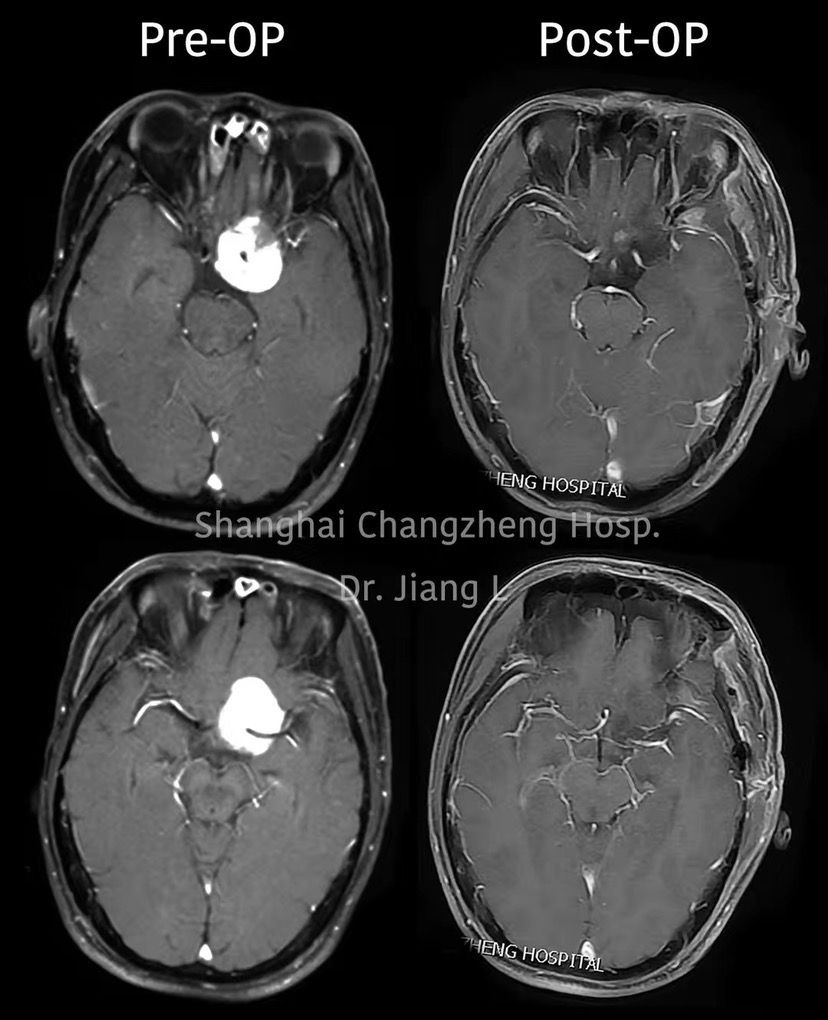

MRI检查:

术后MRI检查提示肿瘤全切。